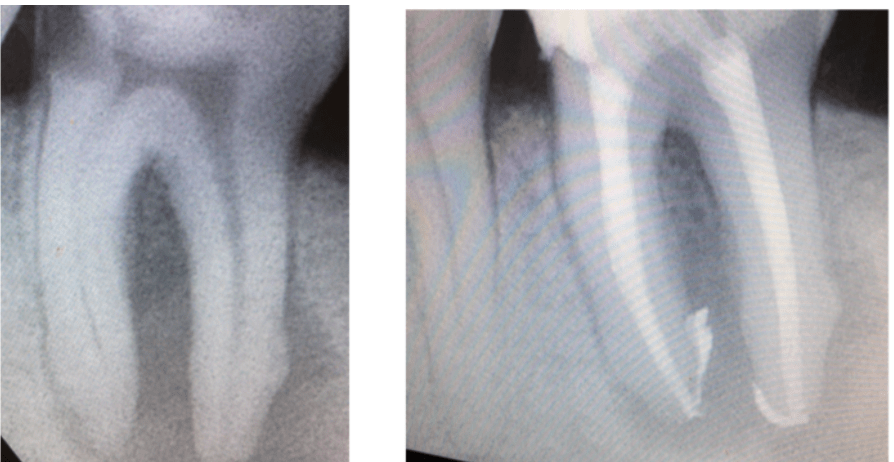

Il granuloma che interessa i denti viene definito “GRANULOMA APICALE”. Si sviluppa intorno all’apice della radice di un dente cariato o colpito da gangrena della polpa oppure già devitalizzato.

Spesso il paziente non manifesta nessun sintomo e la presenza di un granuloma viene scoperta per caso con una semplice lastra in studio o grazie ad una ortopantomografia (la lastra che mostra tutti i denti) eseguita per altri motivi.

E’ possibile eliminare un granuloma apicale eseguendo una corretta devitalizzazione oppure provando, qualora il dente fosse già stato devitalizzato, un ritrattamento ossia una nuova devitalizzazione. E’ importante, soprattutto nei casi di ritrattamento, affidarsi a operatori esperti che abbiano già trattato casi simili con successo.